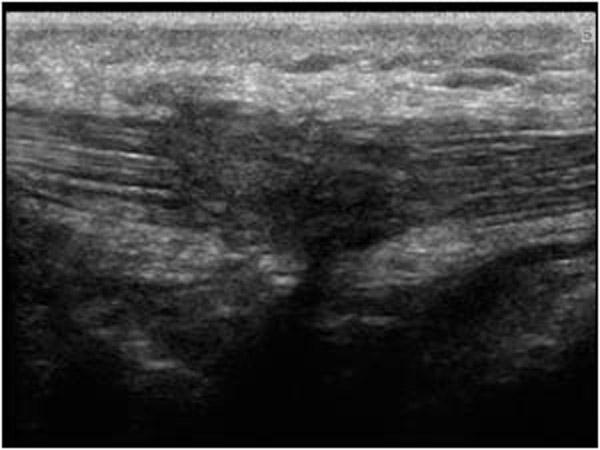

Gallbladder Adenomyomatosis

diverticulum of the GB

Focal, segmental or diffuse smooth muscle proliferation with exaggerated diverticular appearance of the Rokitansky – Aschoff sinuses into the muscular wall